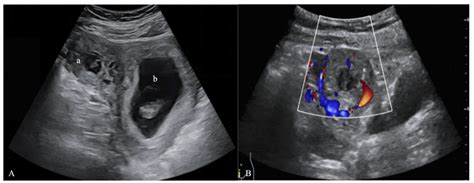

When a physician suspects an ectopic pregnancy, they often perform a transvaginal ultrasound. This procedure uses a specialized wand to provide a high-resolution view of the reproductive organs. By visualizing the uterus, ovaries, and the surrounding areas, radiologists and OB/GYNs look for specific clinical markers.

When doctors look for an ectopic pregnancy by ultrasound, they are essentially looking for an "empty" uterus where there should be a pregnancy sac. The diagnostic process typically involves:

• Identifying the Gestational Sac: In a healthy pregnancy, an intrauterine gestational sac should be visible by the time the human chorionic gonadotropin (hCG) levels reach a certain threshold.

• Locating Adnexal Masses: A mass outside the uterus in the adnexal region (where the fallopian tubes and ovaries are located) often suggests an ectopic implantation.

• Checking for Free Fluid: The presence of free fluid in the pelvic cavity, especially in the pouch of Douglas, can indicate internal bleeding caused by a rupture.